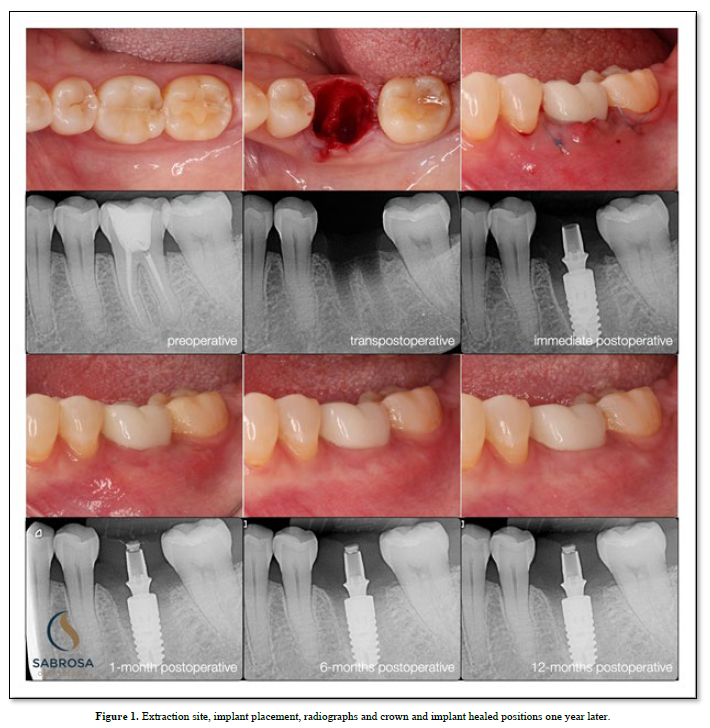

Proprioception is used to navigate space in order for a subject to find a place to make physical contact. (1) An implant with no periodontal housing exhibits little or no proprioception. It has no periodontal housing and no touch or pressure sensors. An opposing functioning tooth with periodontal support is proprioceptive. It is touch sensitive (2). The pressure sensors detect motion and help to reposition and maintain the tooth in a functioning occlusal position. There is little or no information concerning implant proprioception. In a functioning dentition teeth find their position by adjusting to the existing teeth in occlusion. An under occluded implant crown cannot adapt to an existing occlusion without planned occlusal contact guidance. Positional direction and intensity of contact are left to chance. We, as humans, have five senses one of which is touch. Sharks have six senses one of which is touch from a distance (3). Weak electrical signals are used to make contact from afar. Humans can not touch without making physical contact. An implant crown that is under articulated cannot fit into an opposing dentition without making occlusal contact. Total implant placement procedures and restorative healing results are shown (Figure 1). Without implant restorative occlusal contact adjacent teeth and the surrounding dentition adapt to an altered occlusion. Stress distribution is uneven because fewer teeth maintain the occlusal load. Missing limb syndrome where the patient assumes limb retention upon fitting a prosthetic device may be applied to replacing missing teeth where the patient upon tooth replacement immediately assumes past functioning habits. In this case, as shown, tooth and jaw movements related to an altered occlusion are slight but tooth movements are discernible. The occlusal patterns have shifted. There is an uneven amount of occlusal contact upon the second molar (Figure 2). One year later the occlusal contact areas are more evenly distributed. The implant restoration is in functional occlusion. The second molar now fits into the occlusal scheme as does the first molar implant restoration. The teeth have been realigned (Figure 3). In order to plan the occlusion of this implant the clinician (CES) adjusted the surface of the milled zirconia crown (Cerec) prior to completion so that it would just make occlusal contacts upon hard closure (Figure 2). Clinical acumen dictates how much occlusal clearance is required. It is estimated that teeth intrude up to 100 microns upon occlusal loading (3). We assume that when the tooth is fully loaded it will make occlusal contact with its antagonist but when not loaded it will not make contact (4) (Figure 2). To verify contact and non-contact we make a silicone inter occlusal record at the time of insertion (5). The impression is removed and immediately processed using a specially made occlusal scan which includes a direct current light box positioned six inches from an enclosed overhead camera which is connected to an image producing means for recording and interpreting various thicknesses of impression material. The results using image analysis (Image J) can be assessed numerically or viewed using assigned colors that relate to the numbers (6). Two hundred fifty-six pixels is the baseline and the color is white (contact).